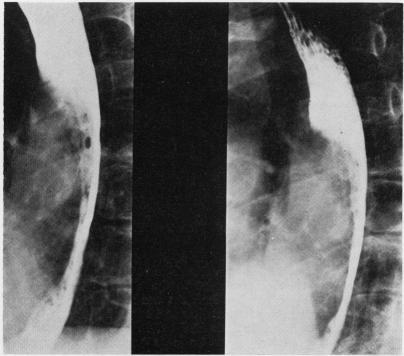

Spontaneous intramural rupture or intramural haematoma of the oesophagus is a rare cause of acute pain in the chest and upper abdomen. Much less ominous than spontaneous complete rupture from which it must be distinguished, it seldom if ever necessitates operation. Five new cases are described and reviewed together with 15 collected from published reports. The dominant symptom of every case was severe and constant retrosternal or epigastric pain; concomitant dysphagia was mentioned in 11 cases. In seven the pain was preceded by or coincided with vomiting. The condition was related to other stresses in three and appeared to be truly spontaneous in 10. In approximately one-third of cases it started suddenly but more often it began as discomfort worsening rapidly. Fourteen patients vomited blood after experiencing pain but only four were given transfusions. In contradistinction to complete rupture, none had surgical emphysema and plain chest radiographs were unremarkable. All had abnormal gastrografin or barium swallows. Intramural haematomas with or without mucosal tears were seen in the 11 cases in which oesophagoscopy was performed. Fifteen patients made rapid and complete recoveries on conservative management. Of the four who did not respond satisfactorily, one had the oesophagus repaired, two had drainage of the mediastinum after failure to find the false lumen at thoracotomy, and one had only an abdominal exploration. The only death in the whole series occurred after a disastrous emergency exploration and subsequent total oesophagectomy.

食管自发性壁内破裂或壁内血肿是引起胸部和上腹部急性疼痛的罕见原因。与必须与之鉴别的自发性完全破裂相比,其凶险程度要低得多,很少需要手术治疗。本文描述并回顾了5例新病例,并结合从已发表报告中收集的15例病例进行分析。每例的主要症状均为严重且持续的胸骨后或上腹部疼痛;11例提及伴有吞咽困难。7例疼痛发生在呕吐之前或与呕吐同时出现。3例与其他应激因素有关,10例似乎是真正的自发性。约三分之一的病例起病突然,但更多情况下起初表现为不适且迅速加重。14例患者在疼痛后呕血,但仅4例接受了输血治疗。与完全破裂不同,无一例出现手术性气肿,胸部X线平片无明显异常。所有患者的胃造影或吞钡检查均有异常。在接受食管镜检查的11例患者中,可见有或无黏膜撕裂的壁内血肿。15例患者经保守治疗后迅速完全康复。4例反应不佳的患者中,1例行食管修复术,2例开胸手术未找到假腔后行纵隔引流,1例仅行腹部探查。整个系列中唯一的死亡病例发生在一次灾难性的急诊探查及随后的全食管切除术后。